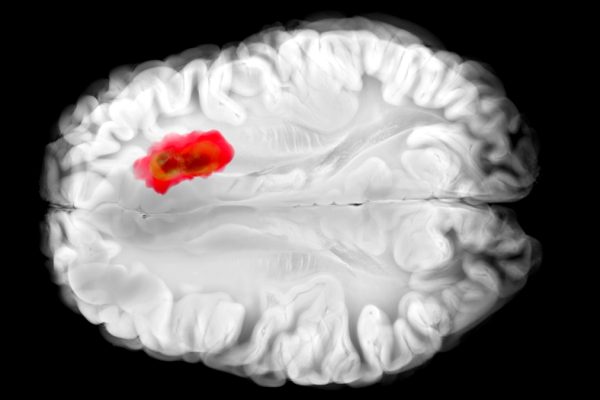

Descoperire importantă: Un Medicament Comun Pare să Lupte împotriva unuia dintre Cele Mai Mortale Cancere Cerebrale

Cercetătorii de la Universitatea din Pennsylvania au descoperit că hydralazina blochează o enzimă specifică numită 2-aminoetanetiol dioxygenază (ADO), care este asociată cu glioblastoamele, un tip de cancer cerebral extrem de agresiv. Studiul a arătat că ADO este esențial în procesul de răspuns al organismului la scăderea nivelurilor de oxigen, declanșând o reacție în lanț ce…